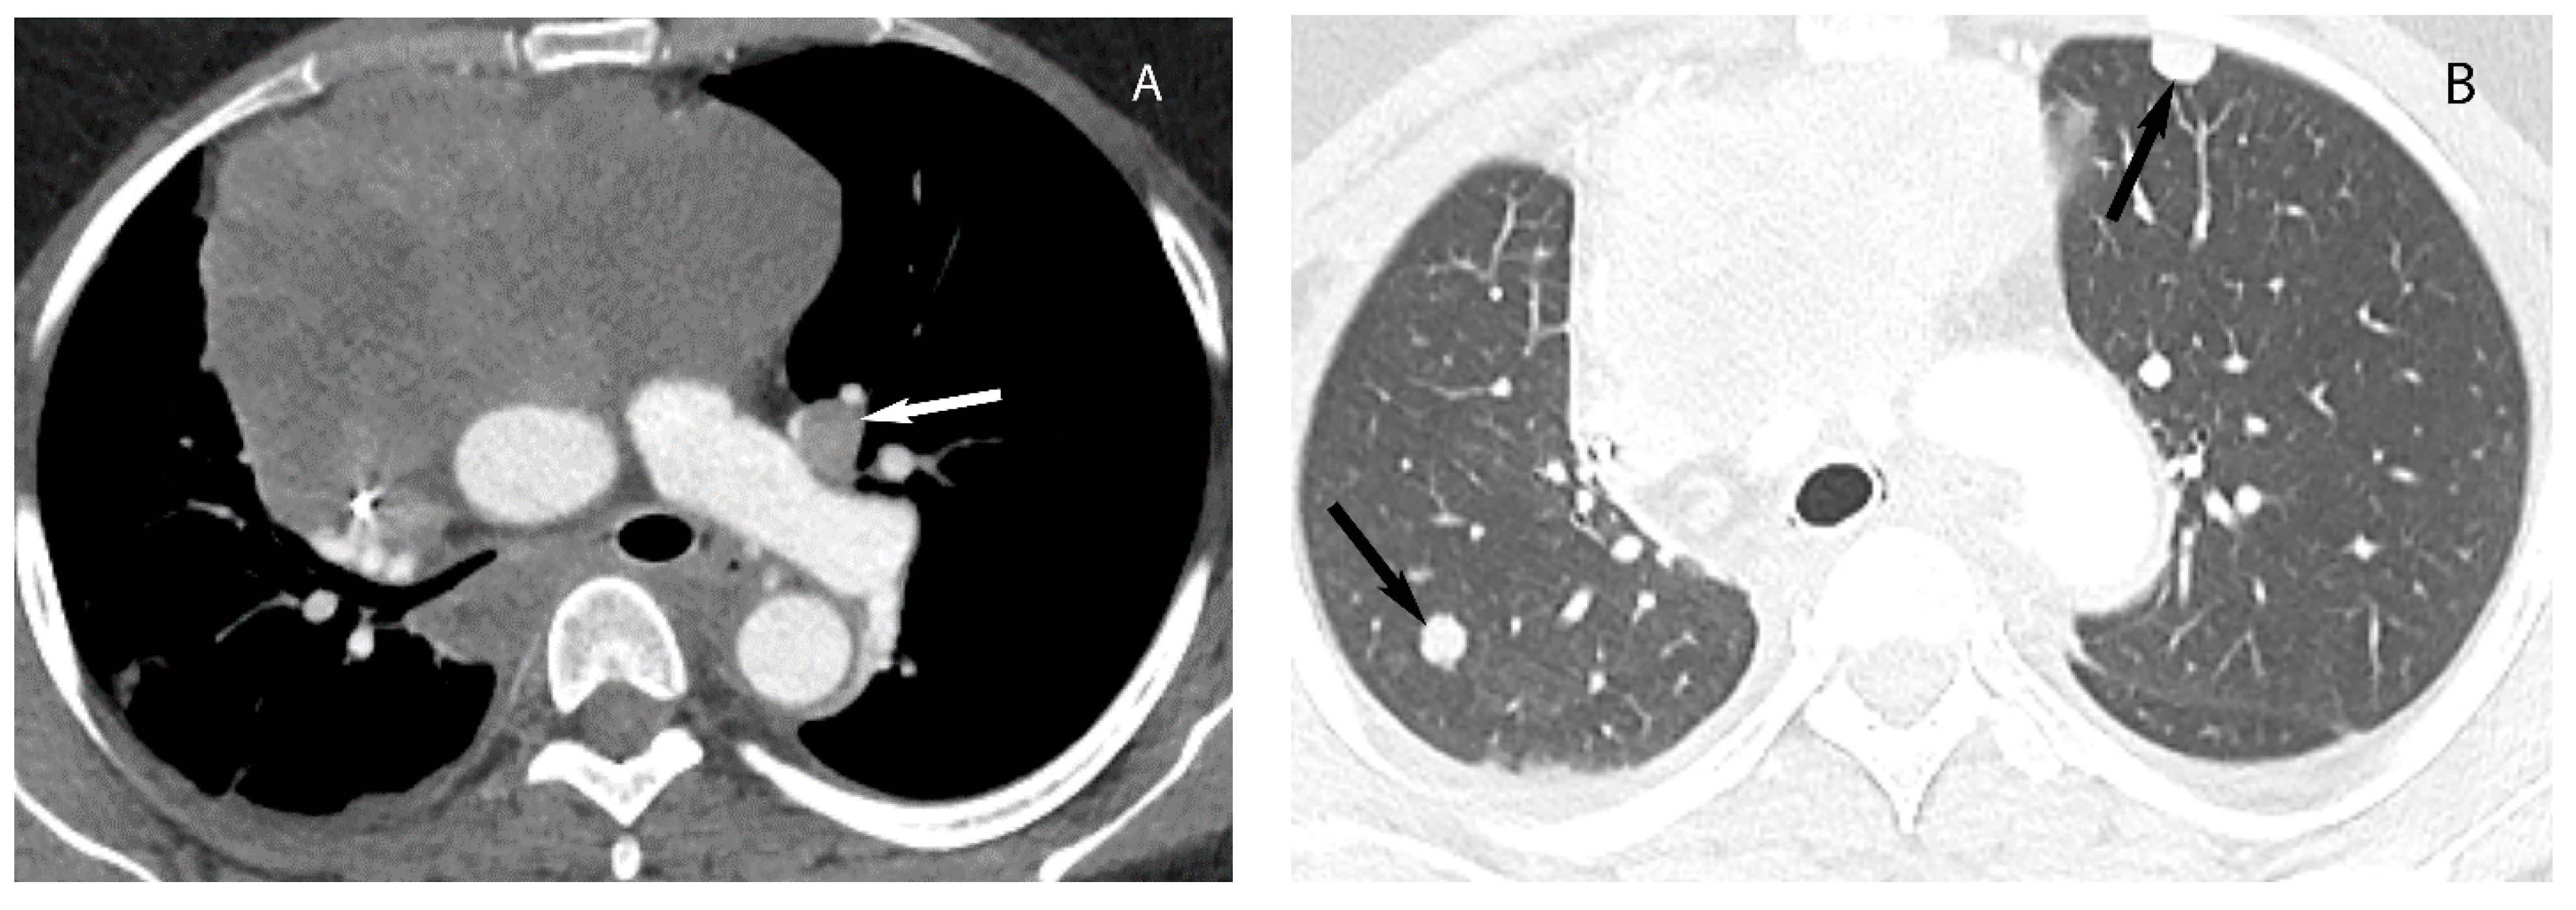

7. Germ Cell Tumors

9. Hypervascular Lesions